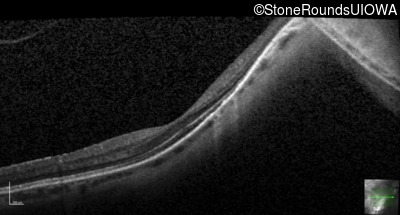

Age at visit: 41 years (Visit 2)

This 41 year old woman was highly myopic as a child and experienced a rhegmatogenous retinal detachment OS at age 20.

The clinical features favoring the diagnosis of Sticker syndrome in this patient include extensive radial lattice degeneration, a personal and family history of rhegmatogenous retinal detachment, a history of cataract surgery before age 30 (and very high myopia before that), arthritis in her knees and hips and a slightly flattened mid-face.